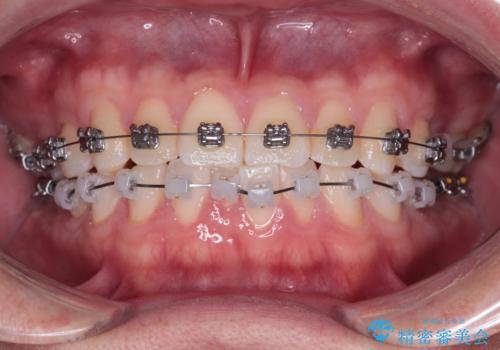

・費用と期間を抑えるために、多少目立っても効率の良いメタルブラケットを使用

・奥歯のシザーズバイト改善には、口蓋側にアンカースクリュー(TAD)を設置し、矯正用ゴムで内側に牽引

・捻転した第二小臼歯は、ワイヤーと矯正用ゴムの力を用いて正しい位置へ回転移動